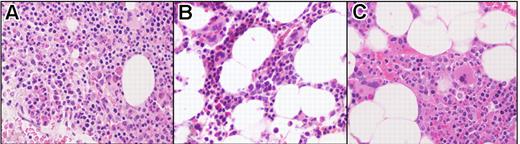

None of the patients developed recurrent symptoms and their eosinophil counts, serum B12, and tryptase levels remained suppressed at the point of initial molecular relapse (Table 2). The 2 patients with cardiac involvement (patients 6 and 7) who remained on 300 to 400 mg imatinib daily have remained in clinical, hematologic, and complete molecular remission for 51 and 56 months, respectively. Bone marrow examination was performed in 2 patients at the time of molecular relapse and was unchanged from the bone marrow obtained at 1 month after treatment (Figure 2). Notably, there was no increase in eosinophilia, cellularity, atypical mast cells, or reticulin fibrosis.

Bone marrow biopsy findings in a FIP1L1/PDGFRA-positive subject (subject 3). Before imatinib treatment (A), at 1 month following initiation of treatment (B), and at the time of molecular relapse (C). Posttreatment resolution of eosinophilia and hypercellularity was maintained despite molecular relapse. Sections were stained with hematoxylin and eosin (H&E), magnification 400×, and images were obtained by digital microscopy using an Olympus BH-Z microscope (Olympus America, Melville, NY) equipped with a DPlan 40 × 10.65 numeric aperture objective. Images were captured using an Olympus DP12 digital camera system and recorded on a 3.3V Smart Media (SSFDC) card. Imaging software was Adobe Photoshop version 6.0 (Adobe Systems, San Jose, CA).